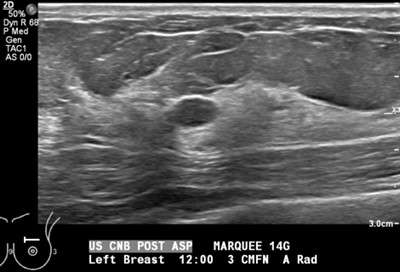

- Technologist saves a final image to document that the cyst has decreased in size and/or completely collapsed (Figure 3).

Figure 3. Post-aspiration grayscale sonogram shows complete collapse of the more posterior cystic structure, indicating that the internal contents have been successfully aspirated.